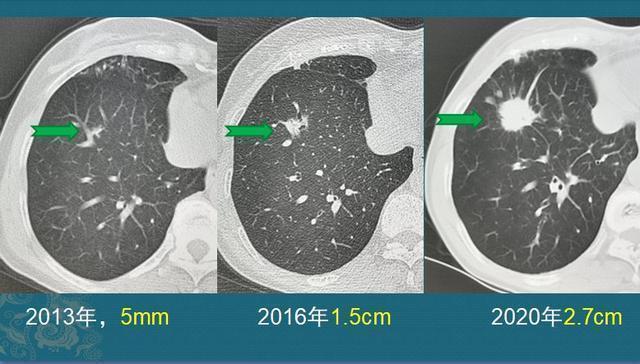

这种混合磨玻璃结节是怎么长大的呢?我们找一个逐渐增大的典型病例,看看混磨的成长过程:

文章插图